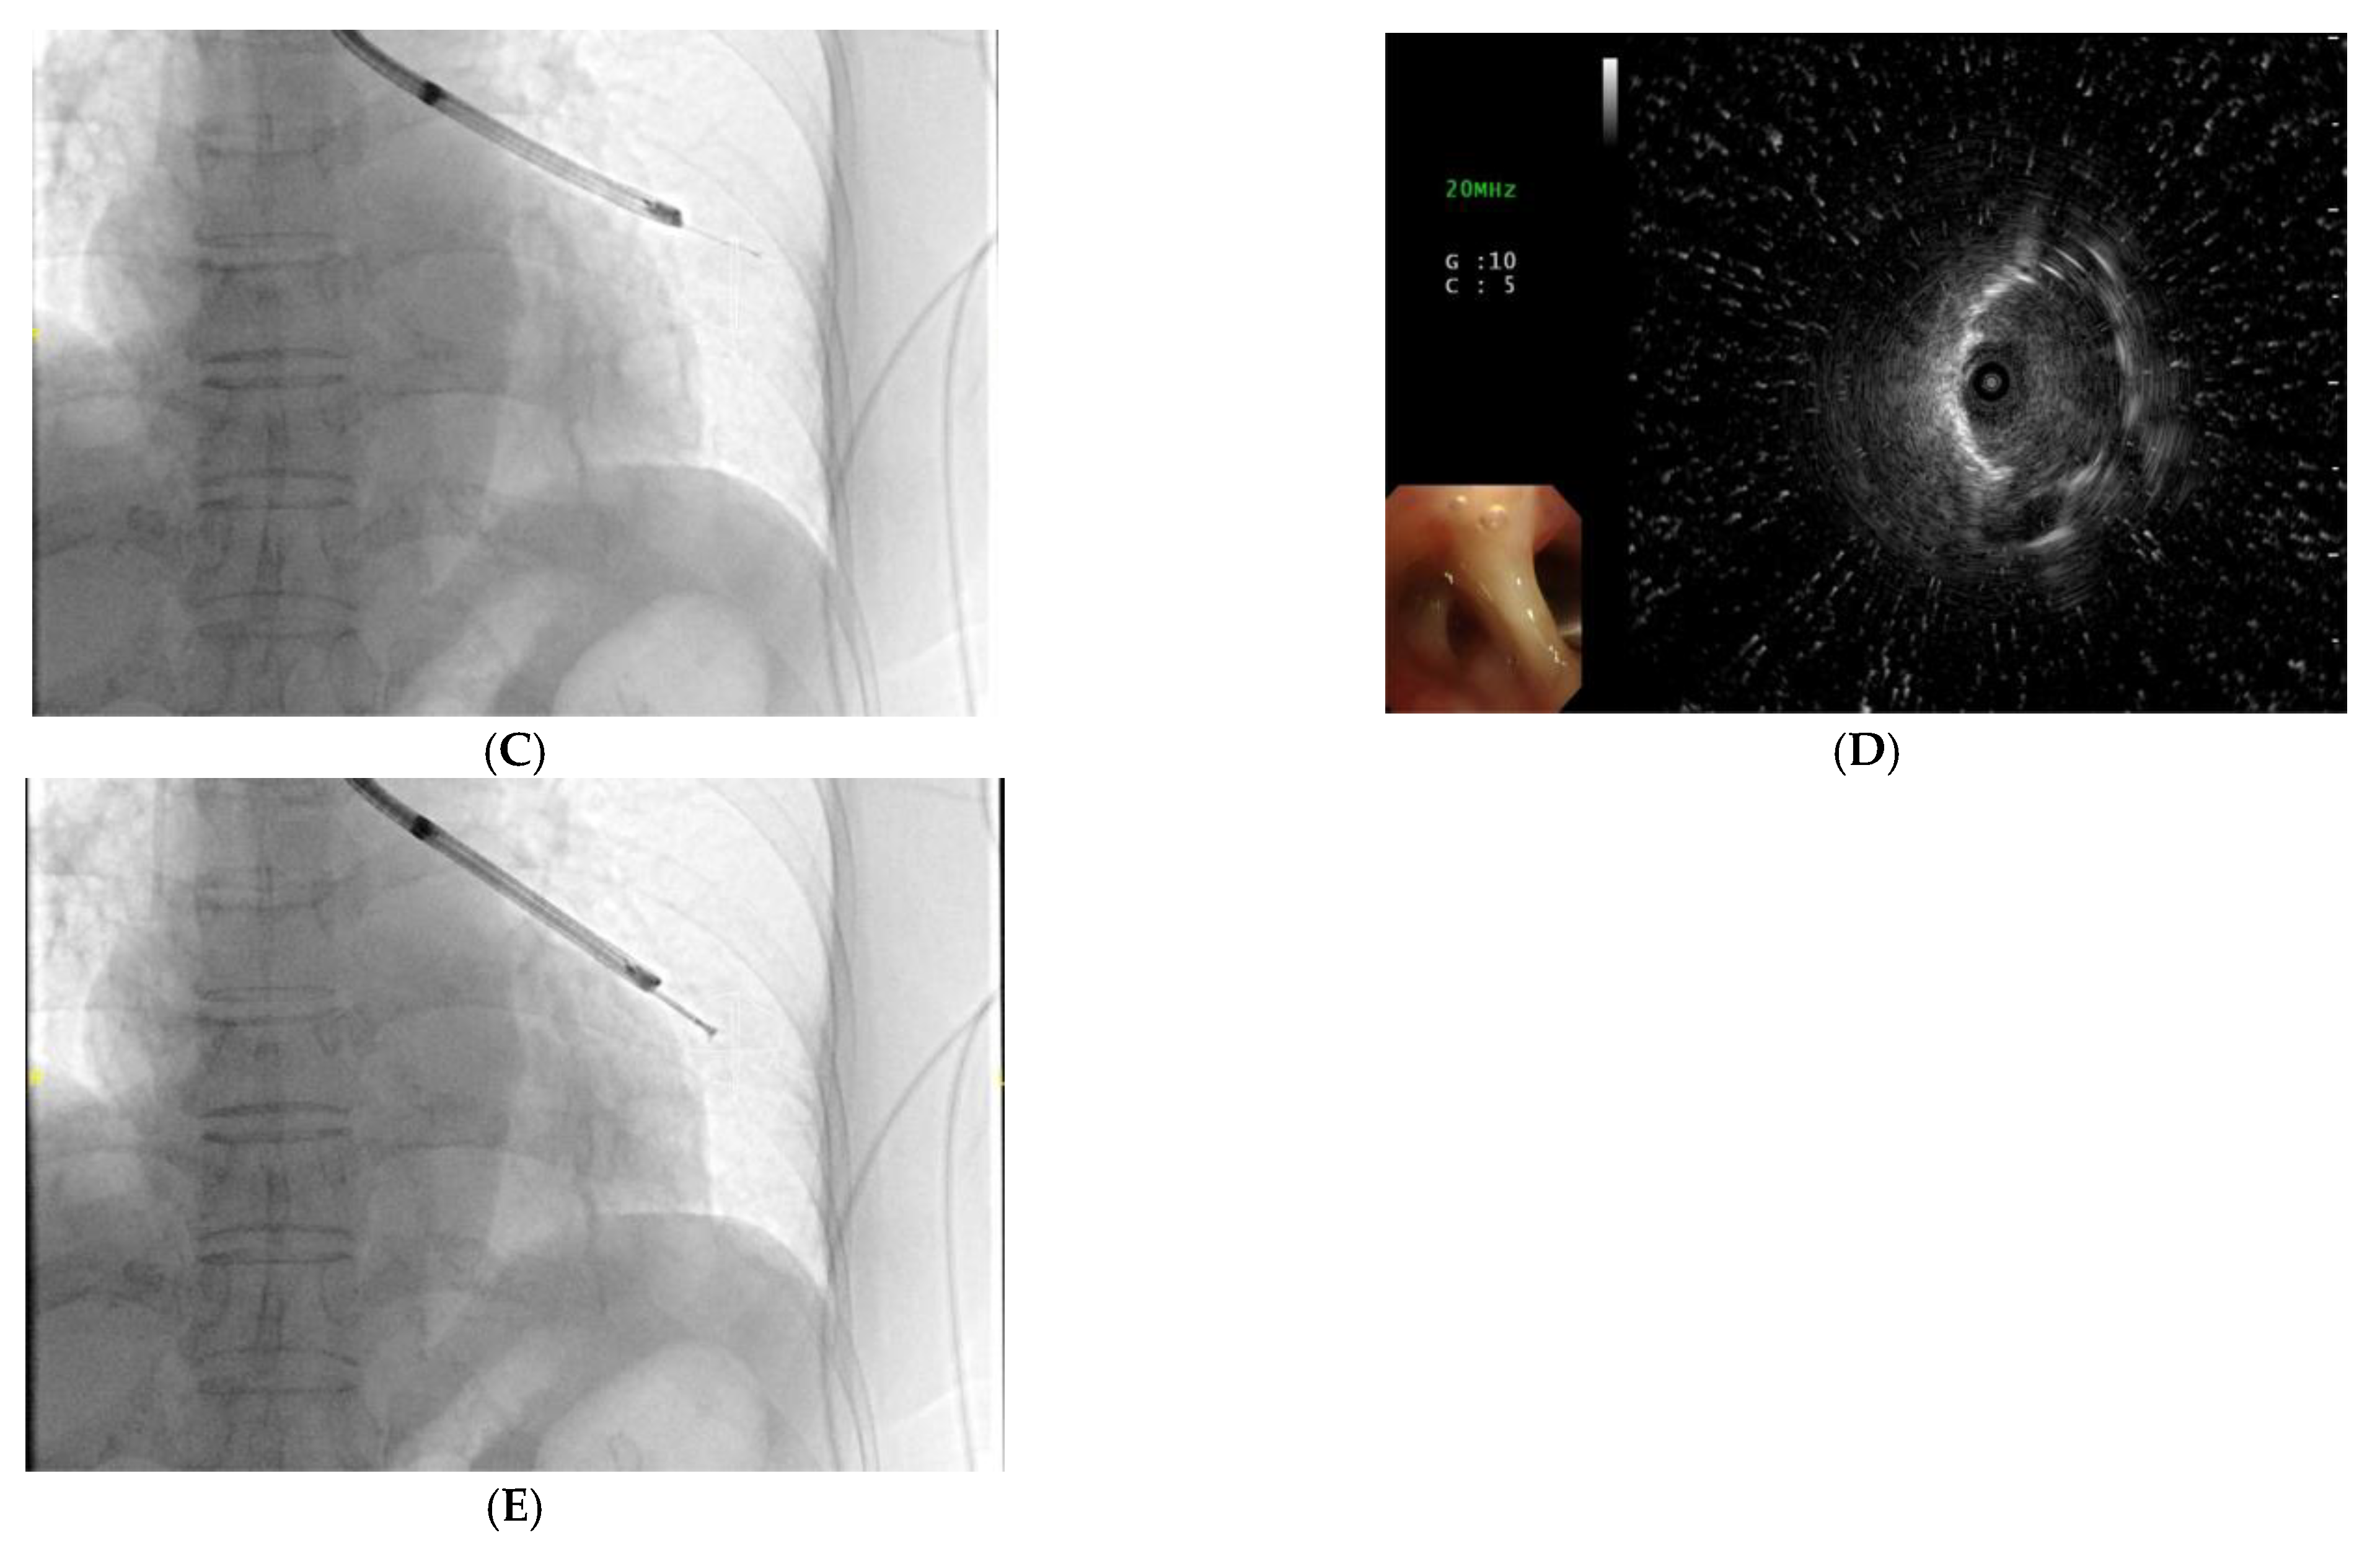

Figure 2.

A 75-year-old female patient received CBCT-AF combined with EBUS-TBB, and was finally diagnosed with lung adenocarcinoma. (A) standard CT image showing a small nodule (10.6 mm) at the left lower lobe; (B) the target lesion on CBCT image contoured in three standard axes for the AF image; (C,D) a concentric peribronchial lesion discovered by radial-EBUS via AF guidance; (E) TBB guided by AF image. AF, augmented fluoroscopy; CBCT-AF, cone-beam computed tomography-derived augmented fluoroscopy; CT, computed tomography; EBUS-TBB, endobronchial ultrasound-guided transbronchial biopsy; TBB, transbronchial biopsy.